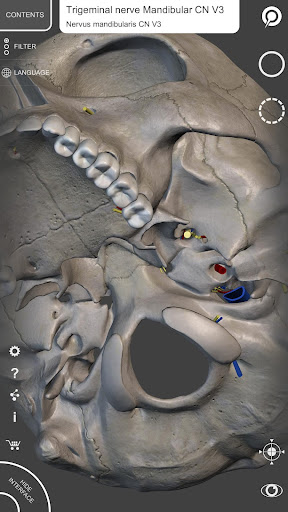

"Skeleton | 3D Atlas of Anatomy" is a next generation anatomy atlas in 3D which gives you availability of interactive highly detailed anatomical models!

Each bone of the human skeleton has been reconstructed in 3D, you can rotate and zoom in on each model and observe it in detail from any angle.

By selecting models or pins you will be shown the terms related to any specific anatomical part, you can select from 12 languages and show the terms in two languages simultaneously.

• The anatomical terms and the user interface are available in 12 languages: Latin, English, French, German, Italian, Portuguese, Russian, Spanish, Chinese, Japanese, Korean and Turkish

• The anatomical terms can be shown in two languages simultaneously